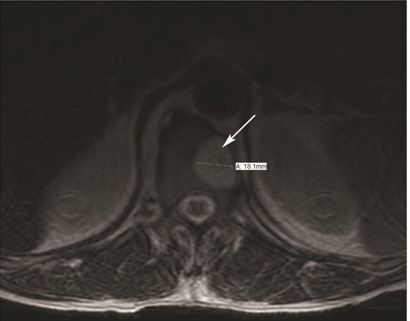

Given the need for long-term anticoagulation the incidental finding of a hemangioma within T12 vertebral body was concerning. Moreover, patient affirmed subjective weakness of both legs for last six months although neurological examination did not reveal any objective evidence of loss of power. Neurosurgical opinion was sought to determine the safety of long-term anticoagulation in presence of the vertebral hemangioma. An MRI performed to assess its invasive nature revealed a well circumscribed T1 hyperintense, T2 hyperintense lesion in the T12 vertebral body with no enhancement. There was no associated soft tissue mass with any involvement of the spinal canal or prevertebral tissues [Table/Fig-4a,b]. No other focal bone lesions were visualised. This benign appearance of the hemangioma deemed the patient to be a safe candidate for long term anticoagulation. He was eventually discharged to home with an enoxaparin bridge to warfarin. Subsequently, he underwent a myocardial perfusion stress test two months after discharge, which did not reveal any ischemic defects.

Transverse section of the MRI spine incidentally showing a hemangioma measuring approximately 18.1 mm (solid white arrow)